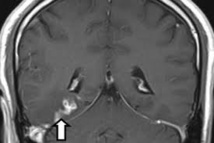

La petite bête, le Spirometra erinaceieuropei, nichait dans le cerveau de cet homme de 50 ans depuis quatre ans, se déplaçant d'un côté à l'autre.